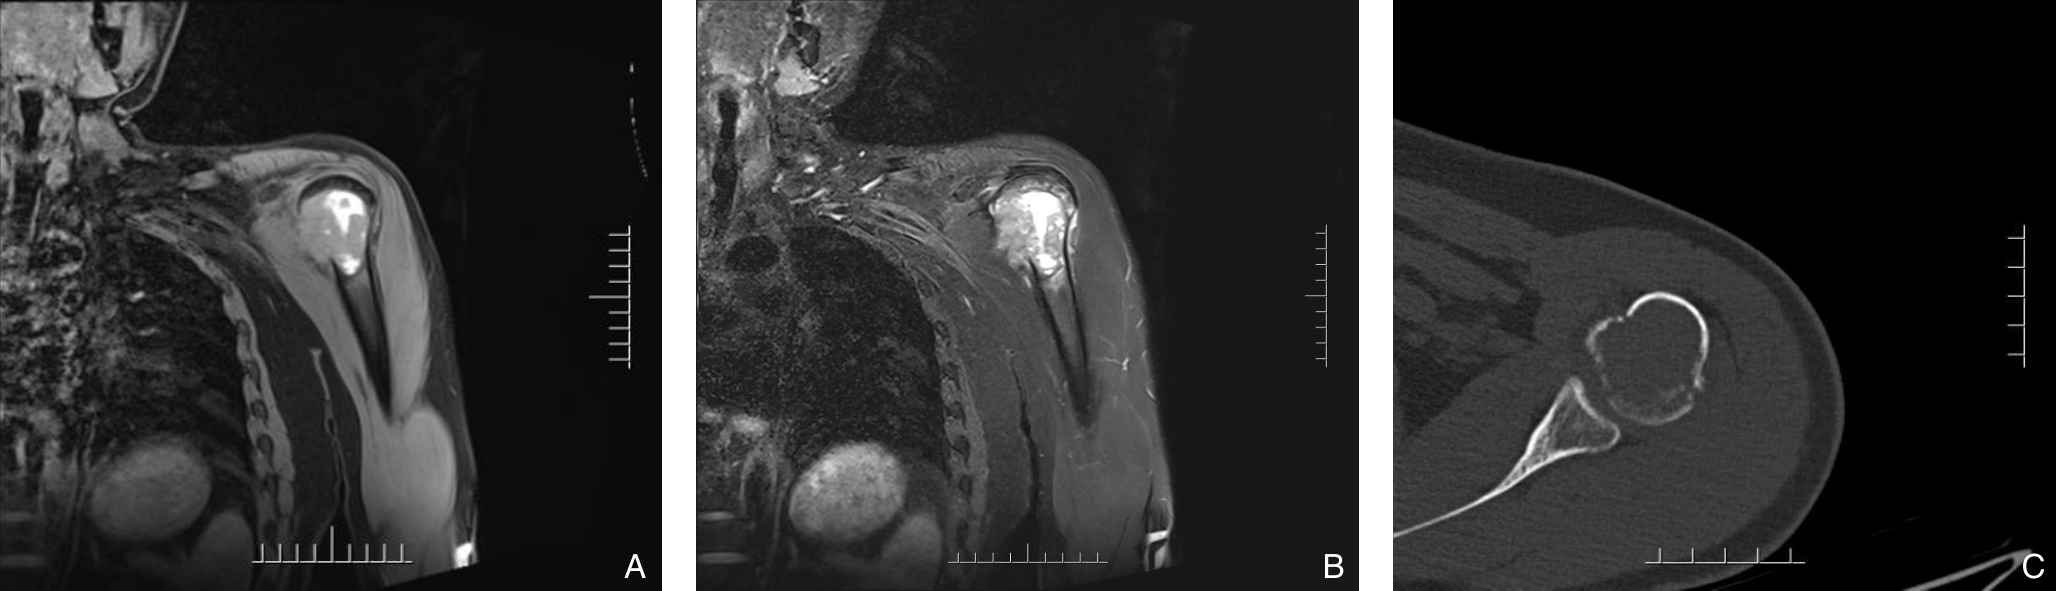

• Occult hepatocellular carcinoma presenting with humeral metastasis as the initial manifestation: a case report and literature review

Abstract:Background and Aims Hepatocellular carcinoma (HCC) presenting initially with bone metastasis is uncommon, and metastasis to the appendicular skeleton is particularly rare. These cases often lack typical liver disease history, elevated alpha-fetoprotein (AFP), or characteristic imaging findings, leading to frequent misdiagnosis or delayed diagnosis. This study reports a rare case of occult HCC presenting with humeral metastasis and reviews the literature to improve clinical recognition and management.Methods The clinical data of a 42-year-old male patient presenting with humeral metastasis as the initial manifestation admitted in August 2025 were retrospectively analyzed, including laboratory tests, multimodal imaging findings, histopathological and immunohistochemical results, treatment, and follow-up outcomes. Relevant literature was also reviewed.Results The patient presented with left shoulder pain. Imaging revealed osteolytic destruction of the left humerus. PET/CT incidentally detected multiple hepatic lesions without significant FDG uptake. Contrast-enhanced ultrasound demonstrated atypical enhancement patterns, initially suggesting a perivascular epithelioid cell tumor. Histopathological and immunohistochemical examination of biopsy specimens from both the humeral and hepatic lesions confirmed moderately differentiated hepatocellular carcinoma with humeral metastasis (CNLC stage IIIb). The patient received systemic therapy with sintilimab plus bevacizumab, followed by transcatheter arterial chemoembolization. After 6 months of follow-up, the intrahepatic lesions had decreased in size, the bone metastasis remained stable, and pain symptoms were significantly relieved.Conclusion HCC presenting with humeral metastasis as the initial manifestation is extremely rare and may lack typical imaging and serological features. Clinicians should consider HCC in patients with unexplained bone metastasis even in the absence of liver disease history or elevated AFP. Multimodal imaging and pathological biopsy are essential for accurate diagnosis and appropriate management.